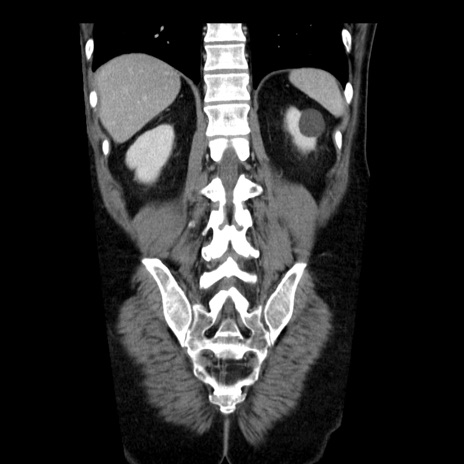

症例29(冠状断像)

【症例】40歳代男性

【現病歴】2日前から胃痛あり。徐々に周期的な激痛に変化した。本日になっても激痛があるため受診。

【身体所見】意識清明、BT 38-39℃台あり、腹部:膨満、やや硬、右下腹部に圧痛あり。

【データ】WBC 8500、CRP 23.26